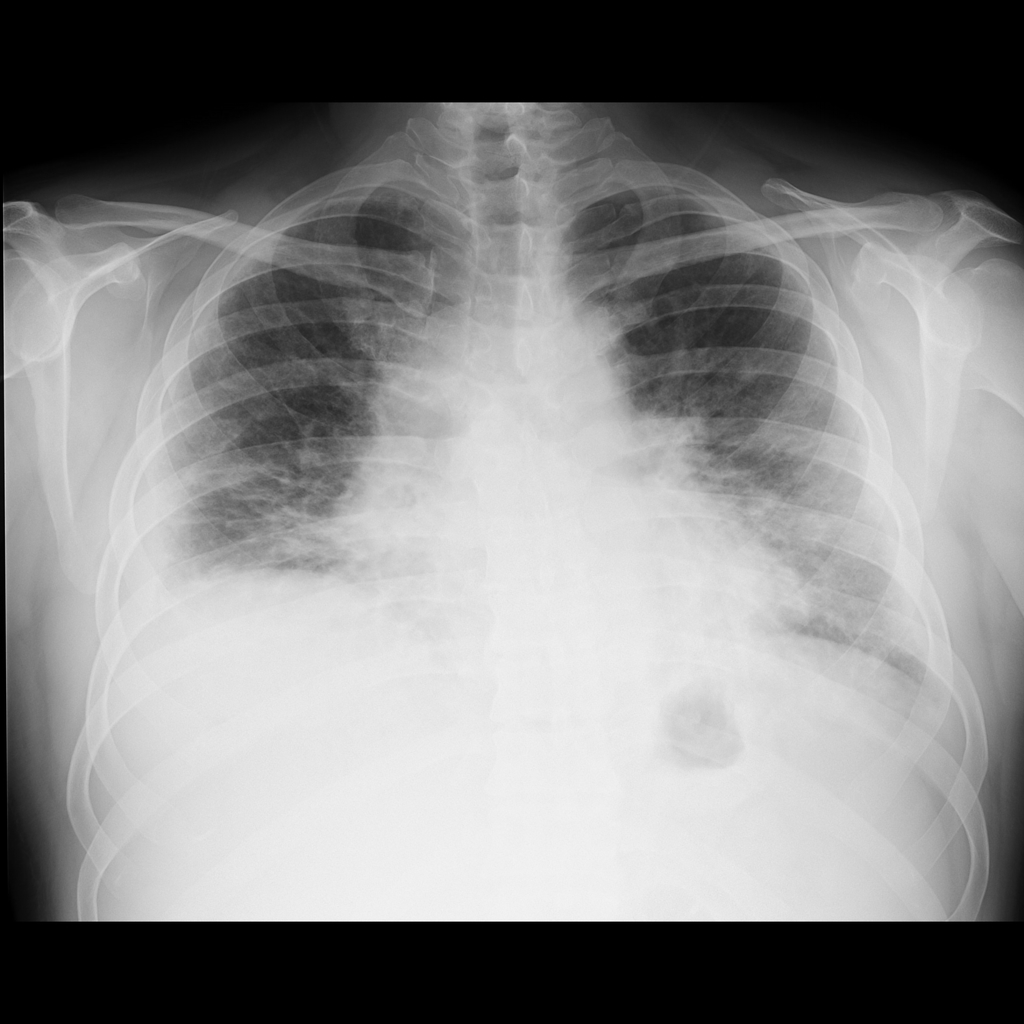

HOMEM DE 45 ANOS DE IDADE REFERINDO DISPNEIA

aumento da área cardíaca, acentuação da trama broncovascular, espessamento intersticial difuso, cefalização de vasos pulmonares, seio costofrênico direito obliterado.

EDEMA PULMONAR CARDIOGÊNICO